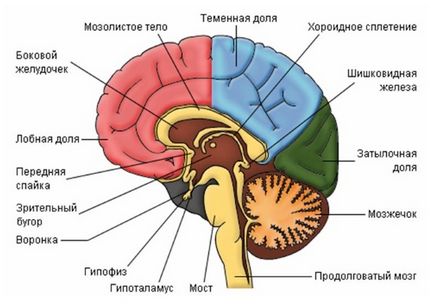

Az evolúció során az emberi agy körül alakult ki egy erős koponya, védi a veszélyeztetett fizikai hatásait a szervezetben. Az agy tovább tart, mint 90% -át a helyet a koponya. Ez három fő részből áll:

Úgy döntött, hogy osztja öt agymetszetekről:

- előagy (agyféltekék);

- hátsóagyat (cerebellum, a pons);

- nyúltvelő;

- középagy;

- középagy.

Ezután jön a hídban - egy tekercs idegrostok kereszt és a szürkeállomány. Ezen keresztül halad a fő verőér táplálja az agyat. Úgy kezdődik, a fenti nyúltvelő, és bemegy a kisagy.

A kisagy két kis félgömbök csatlakozik „féreg”, és fehérállomány és a szürkeállomány, amely azt. Ez a részleg csatlakozik pár „lábak” hosszú híd, a kisagy és a középagy.

A középagy két talamusz, és két hallás (quadrigeminal szervek). Ezekből halmok kiterjeszteni összekötő idegszálak az agyból a gerinc.

Nagy agy elválasztva egy mély hasíték egy kérges test belsejében, amely összeköti a két agyi részben. Minden agyféltekét egy frontális, temporális, parietalis és az occipitalis. Féltekén kiterjed az agykéreg, amelyben az eredete minden gondolkodási folyamatait.

Ezen kívül, három agyi membránok:

- Szilárd képviselő csonthártya a belső felületén a koponya. számos fájdalom receptorok koncentrálódik ebben a héj.

- Arachnoid, amely szorosan szomszédos az agykéregben, de nem bélés gyrus. A tér között, és a kemény héj töltött savós folyadék jellegű, és a tér között, és az agykéreg teli agy-gerincvelői folyadék.

- Lágy, amely egy rendszer a véredények és a kötőszövet érintkezik a teljes felülete az agy anyag, és táplálja.